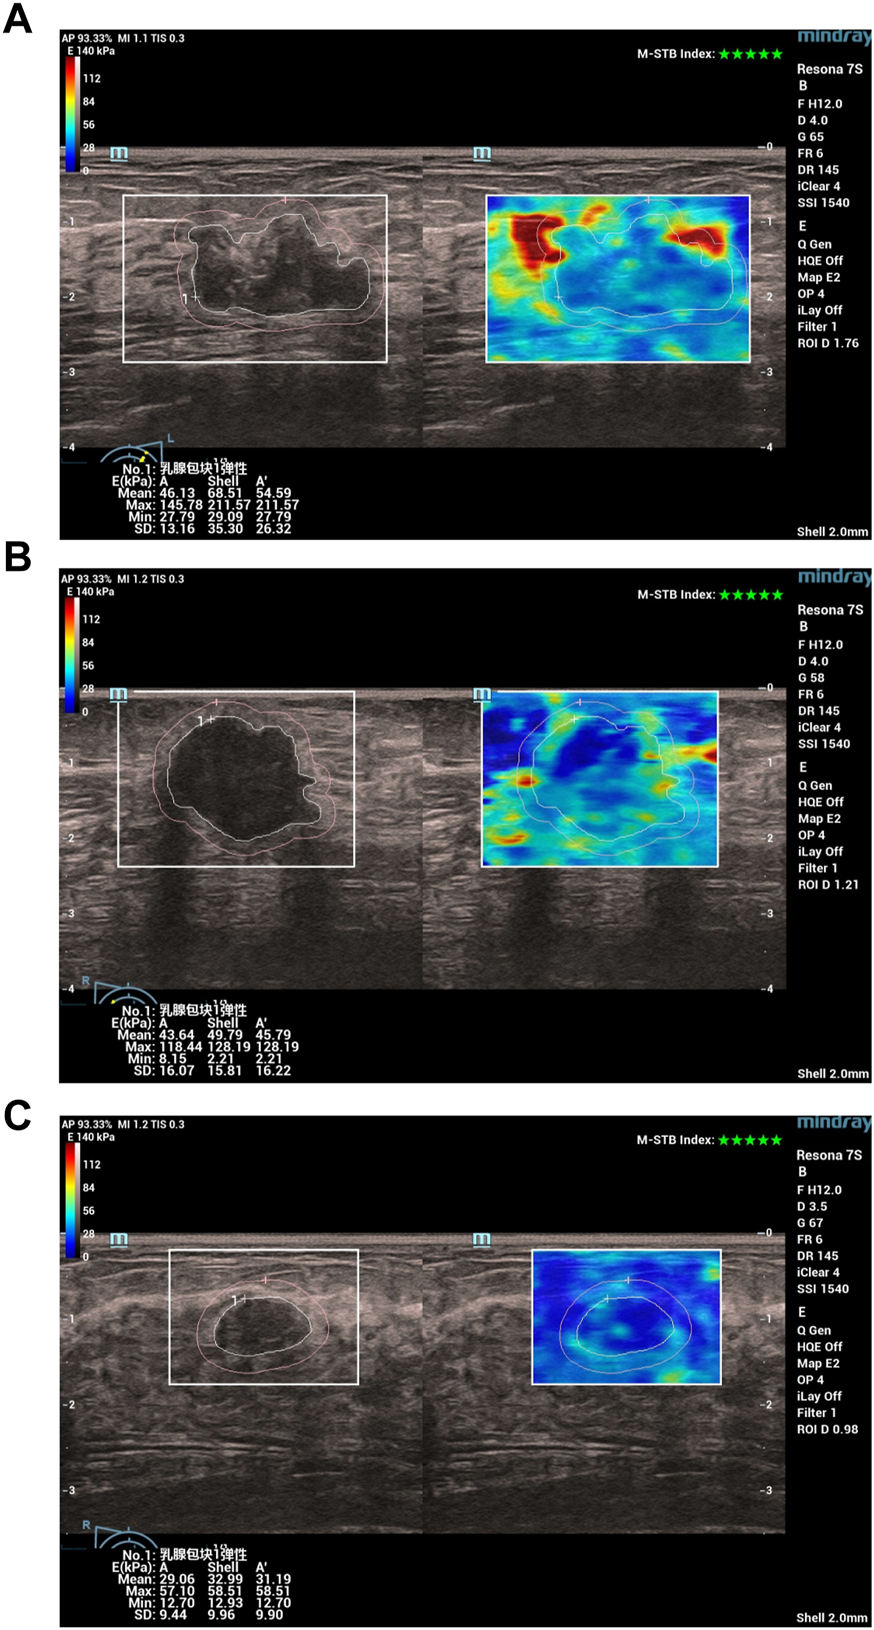

Specifically, all patients first underwent a conventional ultrasound examination. The location, size (maximum diameter), morphology, margins, orientation, echo pattern, microcalcification, and hyperechoic halo of the lesion were recorded. Next, the section with the most abundant blood flow was used to assess the blood flow classification (Adler classification (Adler et al., 1990)) and measured the resistance index (RI). Finally, all patients underwent an ultrasound elastography examination, strain ratio, strain elasticity score, lesion mean elastic modulus (Amean), lesion maximum elastic modulus (Amax), lesion peripheral (shell 2 mm) mean elastic modulus (Smean), lesion peripheral maximum elastic modulus (Smax) were recorded. In Figure 1, we show examples of ultrasound elastography for (a) HER2+ breast cancer, (b) HER-breast cancer and (c) benign breast disease.

FIGURE 1

Examples of ultrasound elastography for (A) HER2+ breast cancer, (B) HER-breast cancer and (C) benign breast disease. Chinese characters 乳腺包块1弹性: in (A–C) stand for “Breast mass 1 elasticity“.